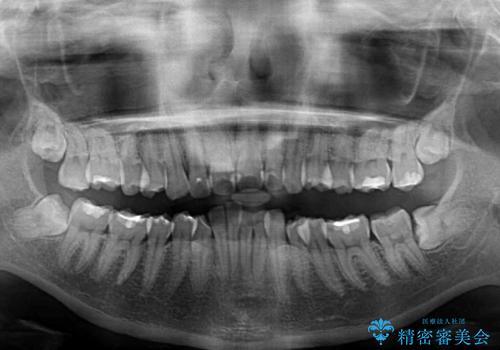

深い咬み合わせと前歯のデコボコ インビザラインによる矯正治療

- 前歯のデコボコと、食いしばりやすい咬み合わせを気にして来院された患者様です。

骨格的に下顎骨が左側に偏位しており、インビザラインでの矯正治療では奥歯の咬みにくさが残る仕上がりが懸念されましたが、新幹線での通院となるため、来院回数の少ないインビザラインでの治療を希望されました。

一方で、デコボコや下顎の前歯が隠れてしまうほどの深い咬み合わせはしっかりと改善されました。